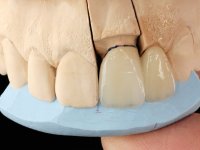

A two element bridge was suggested, using tooth 2.1 as abutment and tooth 2.2 as cantilever pontic. Cantilever bridge with ceramic-coated Zr infrastructure.

Arcade prints were made with irreversible hydrocolloid, for the lab to prepare an acrylic provisional bridge, with tooth 2.1 as abutment and tooth 2.2 as cantilever pontic. A palatal support was made to be bonded with the palatal surface of tooth 2.3. After removal of the Maryland bridge and the vestibular veneer from tooth 2.1, the dental abutment was re-prepared by making the cervical finish line intrasulcular. The provisional bridge made in the lab was relined on the mouth with self-curing acrylic and composite resin. During 6 weeks the soft tissues were worked and stabilized, preparing the consultation for impression. In this session, gingival separation was performed with kaolin paste, using the provisional bridge to compress the material into the gingival sulcus. Impression was performed using wash technique, and the provisional bridge was placed. At the end of the consultation, an impression was made from the provisional bridge placed in the mouth, using irreversible hydrocolloid. The patient had approved the aesthetics of the provisional. This information was passed on to the lab, where the work followed a silicone index, based on the shape and arrangement of the provisional bridge, approved by the patient. The cantilever bridge was built with a Zr infrastructure, with particular care in designing the connector. After being tried and approved by the patient, the prosthetic was cemented in the mouth with resin modified glass ionomer.